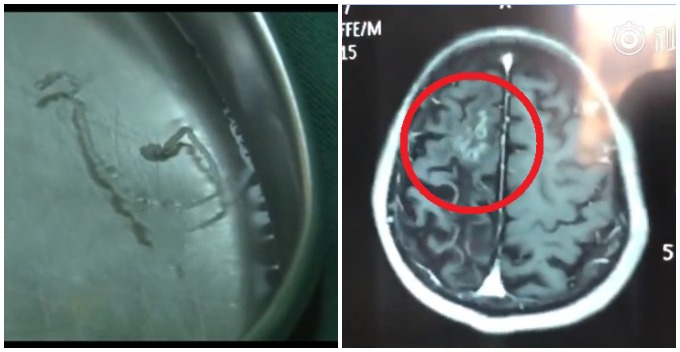

After undergoing scans in the hospital, they finally found the culprit behind all those years of headaches. Apparently, a 10cm parasitic worm had already nestled in his head for years, causing the never-ending migraine.

Source: Miaopai

The parasite was safely removed from Zhang’s skull in a surgery. It was reported that the creature could still be seen actively wriggling even when it was inside the medical tray.